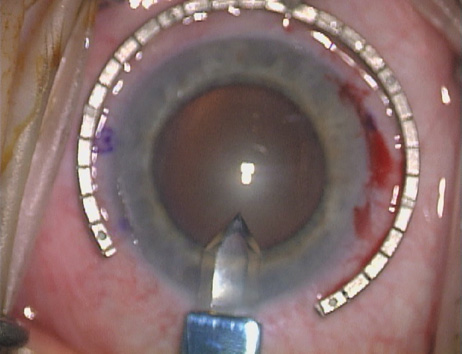

Case 1 is a 68-year-old male who presented for right cataract surgery. His refraction was −1.00 +2.25 × 80 and was recorded as reliable, consistent with his modest cataract density. Keratometry readings were 44.75 × 75 and 43.00 × 165. Corneal topography confirmed slightly more than 2.00 D of regular and slightly oblique cylinder. Consulting the nomogram, a plan was devised for a pair of LRIs to be centered over the 75-degree axis, with each incision delineating 45 degrees of arc. A single plane phaco incision was used and maintained at a size of less than 3.2 mm (Figs. 811).

Fig. 10. The single footplate diamond blade is inserted perpendicular to the corneal surface and at the peripheral most extent of clear corneal tissue. In this case, the nomogram calls for arcuate incisions of 45 degrees. Therefore, the incision is begun approximately 22.5 degrees to one side of the broad hash mark. (Reprinted from Hardten DR, Lindstrom RL, Davis EA. Phakic Intraocular Lenses: Principles and Practice. Thorofare, NJ: SLACK Incorporated, 2004, with permission.)

Fig. 11. Opposite relaxing incision is completed. (Reprinted from Hardten DR, Lindstrom RL, Davis EA. Phakic Intraocular Lenses: Principles and Practice. Thorofare, NJ: SLACK Incorporated, 2004, with permission.)